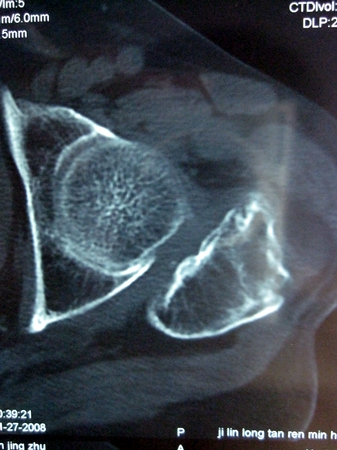

以下是引用lkc8963在2008-12-19 21:19:00的发言:[br]左?右?患侧大转子上移,股骨颈骨质浓杂,髋周见多发条片状骨化影,以小转子为著,多为陈旧性股骨颈骨折后改变并骨化性肌炎.请咨询既往史!